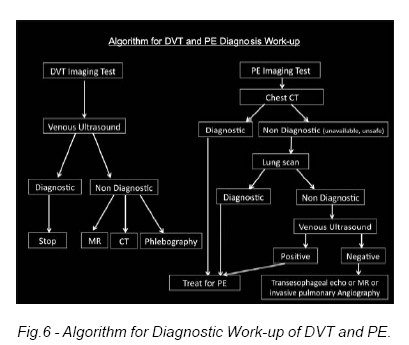

An Algorithm for Diagnostic Work-up can be defined (Fig.6).